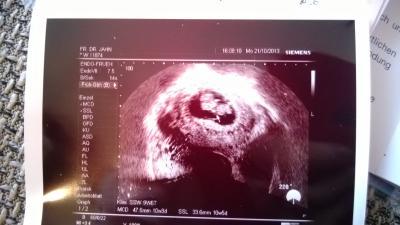

Hy Mädels... ich war Montag (21.10.) erst beim Arzt. Und muss nun bis 25.11. warten.... Das ist doch echt gemein :( Gerade wenn man sich nur schonen darf. Ich nenn das immer "brüten". Nun "brüte" ich seit einer Woche erst richtig bewusst. Und ich mir fällt jetzt schon die Decke auf den Kopf. Bissl sorgen mach ich mir auch ob alles ok ist, oder ob sich am Gebärmutterhals doch was verändert hat? :( Hat zufällig eine von euch auch schon eine Schwangerschaft mit Muttermundschwäche und Verschluss hinter sich, und danach eine normale Schwangerschaft erleben dürfen? Ich guck mir nun täglich mein Zwerg an und rede mit ihm. Mein kleiner redet auch schon mit dem Baby und streichelt es. Das macht mir bissl Mut das es sich lohnt zu liegen und zu "brüten". Ein Bild meines Zwerges hab ich euch mal mit ran gehangen das hatte ich Montag bekommen. Nun ist Wochenende Mädels. Zeit für die Familie. Mein großer feiert morgen seinen 10. Geburtstag. Ich wünsch euch ein schönes Wochenende.

Bild zu Warten , warten , warten ... - Forum für Mai - Mamis